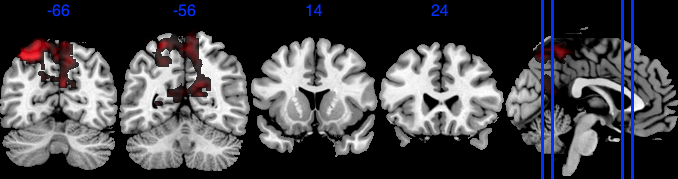

| Posterior inclusion probability (color range ) |

![]() |

| Positive posterior mean of the spatial mediation effects (color range ) |

| Negative posterior mean of the spatial mediation effects (color range ) |

We performed 100,000 iterations for the outcome model (1), discarding the first 50% as burn-in and thinning to retain 1,000 posterior samples. For the mediator model (2), we ran 40,000 iterations with a 30,000 burn-in, thinning every 10 iterations to obtain 1,000 posterior samples. Table 3 gives a summary of both the overall NIE and NDE and the top seven regions identified with the largest number of active voxels. The definition of NIE in each region is , where is the collection of all voxels in region . The rule for selecting the active voxels is based on cutting the posterior inclusion probability (PIP) at 50%, and the three regions with active voxels are reported in Table 3. Due to the very small effect sizes and low signal-to-noise ratio, we also include regions with voxels’ PIP greater than 10%. The posterior of NDE has a mean of 0.27 with the 95% credible interval . The posterior of NIE has a mean of 0.0885 with the 95% credible interval . The total effect of parental education level on general cognitive ability score is 0.36, with 95% credible interval (0.29,0.45). This suggests that parents with college degrees have a positive impact on children’s cognitive abilities, and about 25% of the effect is mediated through brain cognitive development. Figure 5 shows the estimated activation regions and the NIE in coronal view slides. Among the top identified activation regions, the most interesting is the left precuneus, which plays a key role in episodic memory, visuospatial processing, and self-consciousness (lou2004parietal; wallentin2006parallel). This region has been consistently implicated in cognitive processes related to memory retrieval and spatial awareness, which are crucial components of children’s cognitive development. In addition, other identified regions, such as the left inferior parietal region and the left postcentral gyrus, are associated with the interpretation of sensory information (radua2010neural; diguiseppi2023neuroanatomy). These regions are involved in integrating and processing sensory inputs, which are essential for tasks that require coordination between perception and cognition, such as working memory and executive function. These findings align with existing literature on the neural correlates of cognitive function, particularly in children. By identifying regions that have been consistently associated with cognitive processes, our results not only demonstrate the scientific validity of the BIMA approach but also provide meaningful insights into the brain areas that underlie cognitive abilities as captured by the ABCD study.